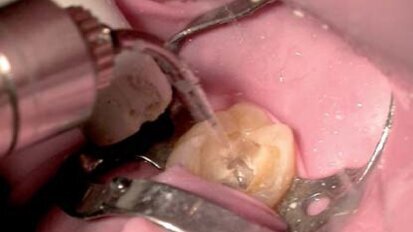

Leczenie wspomagane komputerowo z wykorzystaniem technologii CAD/CAM i CBCT

Jeszcze do niedawna moi pacjenci uznaliby, że pełne leczenie z wykonaniem ceramicznej korony lub mostu podczas jednej wizyty to fikcja. Technologia ...